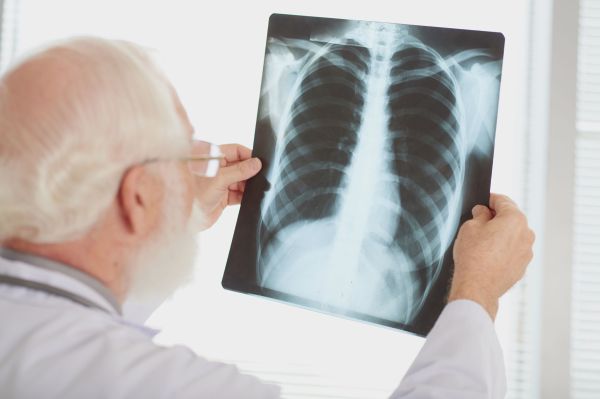

Os principais sintomas da doença, de acordo com Emanoela, são tosse seca por duas semanas, produção de catarro, febre, sudorese, cansaço, dores no peito e falta de apetite.

A especialista alerta que nos primeiros sintomas, o essencial é procurar uma Unidade Básica de Saúde (UBS), para iniciar o tratamento que pode levar de seis meses a um ano. “O tratamento é totalmente gratuito pelo SUS e é muito importante, pois a doença é infectocontagiosa e pode acometer mais pessoas, caso o paciente não faça o tratamento corretamente”, pontua.

Para a prevenção da doença, a docente reforça a importância da aplicação da vacina BCG em crianças. “A primeira medida de controle é a vacina BCG (Bacilo de Calmette e Guérin) que deve ser aplicada nas primeiras 12 horas após o nascimento, ainda na maternidade”, ressalta a especialista.